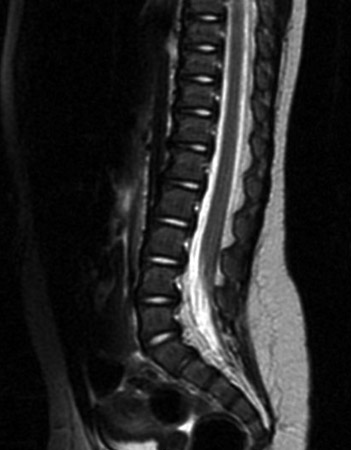

Ressonância nuclear magnética (RNM) da coluna apresentando medula presa

Do acervo do Dr. Nienke P. Dosa; usado com permissão